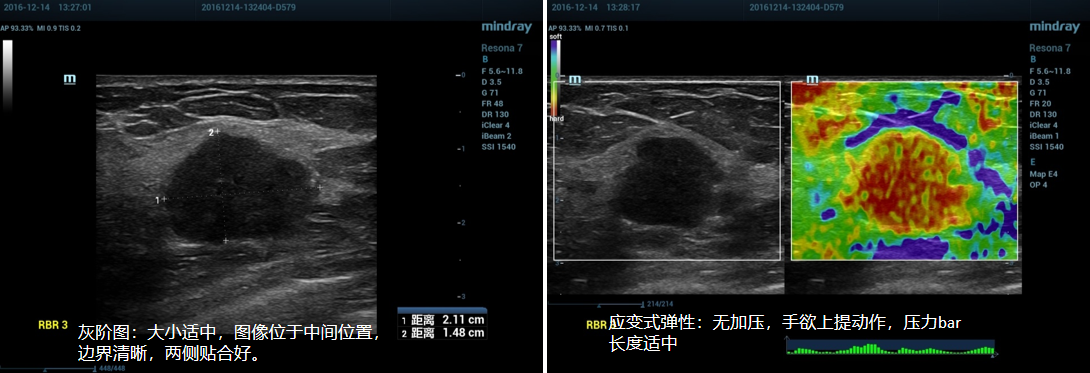

①探头垂直皮肤,勿施加压力,无加压。

②启动Elasto ,选择Strain。压力bar长度适中。

③取样框大小及位置:取样框肿块置于感兴趣区中心位置;大小适中,至少两倍于病变,感兴趣区需包括肿块周围部分正常腺体或脂肪组织。

④嘱患者屏住呼吸,待弹性图像稳定后稍上提探头,脂肪层或腺体层将出现蓝色区域,待图像稳定后,冻结图像。

(1)乳腺应变式弹性成像(脂肪层出现蓝色带):